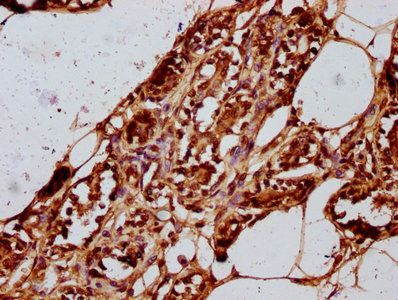

IHC image of CSB-PA010403OA15nme1HU diluted at 1:20 and staining in paraffin-embedded human breast cancer performed on a Leica BondTM system. After dewaxing and hydration, antigen retrieval was mediated by high pressure in a citrate buffer (pH 6.0). Section was blocked with 10% normal goat serum 30min at RT. Then primary antibody (1% BSA) was incubated at 4°C overnight. The primary is detected by a biotinylated secondary antibody and visualized using an HRP conjugated SP system.

IHC image of CSB-PA010403OA15nme1HU diluted at 1:20 and staining in paraffin-embedded human adrenal gland tissue performed on a Leica BondTM system. After dewaxing and hydration, antigen retrieval was mediated by high pressure in a citrate buffer (pH 6.0). Section was blocked with 10% normal goat serum 30min at RT. Then primary antibody (1% BSA) was incubated at 4°C overnight. The primary is detected by a biotinylated secondary antibody and visualized using an HRP conjugated SP system.